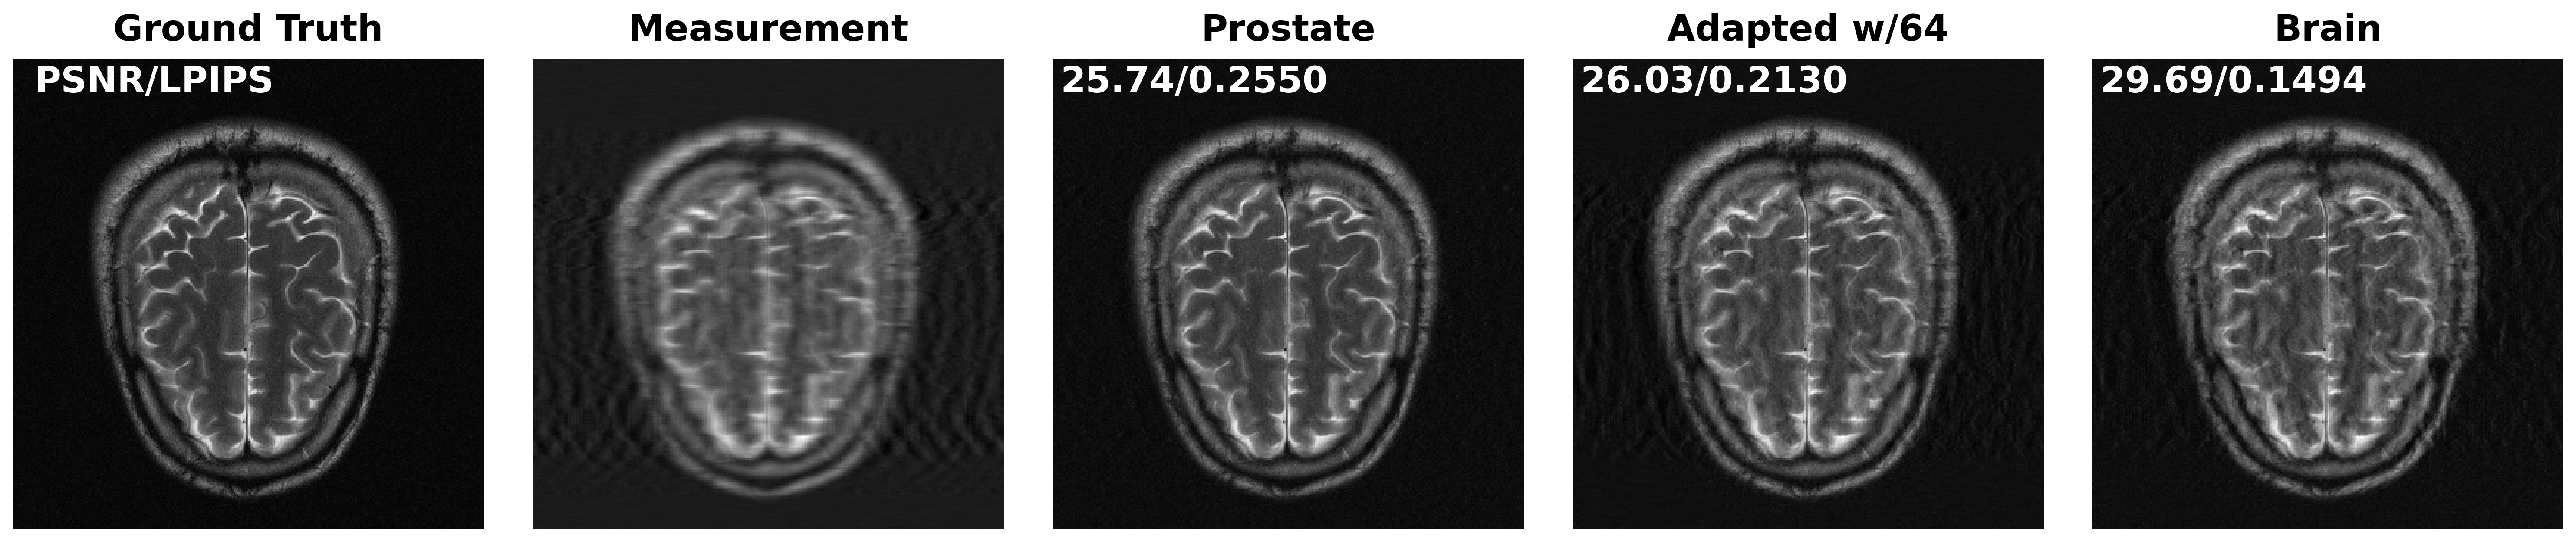

We evaluate the impact of distribution shift—and adaptation on addressing it—on imaging inverse problems. We focus on solving image inpainting using DPS [17] with four models: an InD model (FFHQ), an OOD model(AFHQ), and the AFHQ model adapted using and projected measurements from FFHQ. The adaptation procedure fine-tunes the OOD model to better approximate the score function on corrupted projected measurements from the InD, without using clean images.

Figure 5 presents a visual comparison of inpainting results on a test image from FFHQ under an inpainting mask with sampling probability and measurement noise level . PSNR and LPIPS metrics are reported. As expected, the OOD model performs poorly on the InD data, while adaptation using projected measurements improves visual quality. Table 1 quantitatively compares DPS reconstruction quality across models and measurement settings. Notably, the adapted models show clear gains over the unadapted OOD model, confirming that even partial measurement-based adaptation helps shrink the distribution shift.

| Prostate | ||||

| Knee | ||||

| Brain | ||||

| \cdashline1-5 Adapt64 (Prostate) | ||||